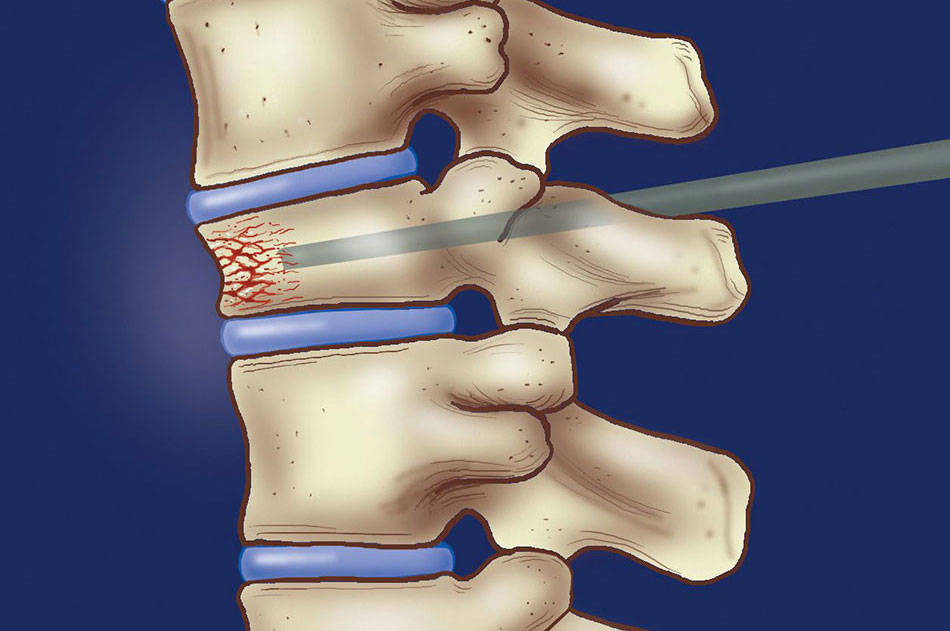

The spinal column is made up of thirty-one individual bones called vertebrae. When they become weakened either because of disease or secondary to medications, they can break or collapse. This is called a compression fracture. Sometime a tumour grows in the bone and weakens it and can cause a compression fracture.

Since it is not possible to immobilize the vertebra completely, patients can have severe pain with movement or secondary to nerve compression. In the past, the only way that this problem was treated was with bed rest, narcotic medication, and in some cases back bracing.

Now, endovascular neurosurgeons are able to offer a procedure called percutaneous vertebroplasty. This procedure is done under radiological guidance, so safe needle placement can be monitored closely. The neurosurgeon inserts a small needle directly into the vertebral body that is compressed. Once needle placement has been confirmed, Polymethylmethacrylate, a type of bone cement, is injected. This essentially strengthens the bone from within.

This procedure has been very effective in decreasing pain, decreasing medication usage, and increasing patient mobility, and is also very safe.